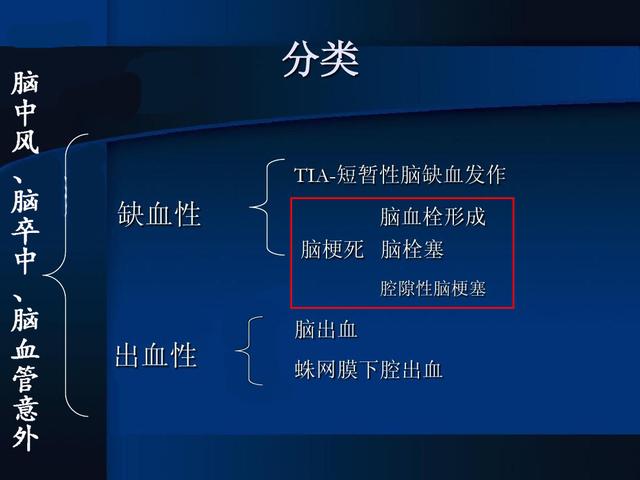

まず、脳卒中、脳梗塞、脳血管障害、この3つは同じ意味だが、人によって呼び方が違う。例えば、言葉が不明瞭になる、口が曲がる、片側の手足が弱くなる、このような症状に対して、私たち庶民の最初の反応は「脳卒中かもしれない」だが、病院では「脳卒中」または「脳血管障害」と呼ばれる。このように、前者は一般的な呼び名であり、後者は医学用語である。

その分類をよりよく理解するために、以下の図にまとめた:

まず脳梗塞について。この用語は現在一般的に使われているもので、血液の供給が途絶える特定の原因によって、脳の特定の領域で神経細胞が壊死することに焦点を当てたものである。虚血の原因によって、脳梗塞にはさまざまなタイプがあります。太い血管の梗塞であれば、重篤な神経障害を起こすことがある。細い血管の閉塞であれば、少量の神経細胞死は起こるものの、神経障害の臨床症状はないことがあり、これは空洞性脳梗塞とも呼ばれる。頭蓋内灌流が不十分なために、2つの血液供給領域の接合部で神経細胞死が起こる場合、これは血流の遮断が特定の血管から脳への塞栓の流入による場合は脳塞栓症と呼ばれる。

(1)脳塞栓症:血液中の塞栓(主に心臓から)が血流とともに脳動脈に入り、血管を閉塞することにより、血液が供給されている部分の脳組織が壊死する。

(2)脳梁性脳梗塞:大脳半球や脳幹の深部にある細い貫通動脈で、長期の高血圧を基盤として血管壁に病変が生じ、内腔が閉塞して小さな梗塞巣が形成される。

(3) 脳分水嶺梗塞:脳の隣接する血液供給源の間の辺縁帯に発生する梗塞。

1、まず脳梗塞とは何かについて、脳梗塞は虚血性脳卒中(脳虚血性脳卒中)とも呼ばれ、脳の血液供給の障害、虚血、低酸素を指し、その結果、脳組織の虚血壊死や軟化が制限される。脳梗塞の一般的な臨床型は、脳血栓症、ラクナ梗塞、脳塞栓症である。